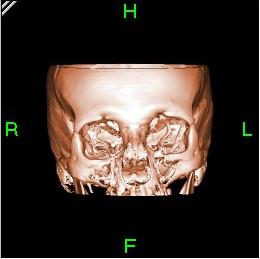

تعود تسميتها إلى كون هذه الطريقة تعطى صورًا شعاعية على شكل مقاطع للجسم، يجري التصوير المقطعي المحوسب بواسطة جهاز خاص، يسمى جهاز التصوير المقطعي المحوسب أو الماسحة المقطعية المحوسبة، تتميز هذه الطريقة بدقتها، تعطي صورًا واضحة، ويمكن أن تعطي صورًا لأماكن قد تكون من الصعب تصويرها بالتصوير الشعاعي التقليدي، كذلك يمكن عملها بشكل سريع ودقيق.

يمكن للأطباء أن ينظروا داخل جسم المريض عن طريق طلب إجراء مسح للعظام والأوعية الدموية والأدمغة والأنسجة الرخوة بفضل ماسح التصوير المقطعي الحاسوبي (CT). بعد إجراء أول فحص طبي بالأشعة المقطعية للمريض في عام 1971، استخدم أطباء الأشعة عمليات المسح لتشخيص الأورام والصدمات والتخطيط للعلاج الطبي والجراحي والإشعاعي في جميع أجزاء جسم الإنسان تقريباً.

داخل الجهاز على شكل كعكة الدونات، حيث يستلقي المرضى على الطاولة بينما يتحرك ببطء عبر الماسح الضوئي، تدور الآلة حولها. أثناء دورانه، يرسل شعاعاً رفيعاً من الأشعة السينية عبر الجسم، والذي يتم جمعه على الجانب الآخر من الجهاز ونقله إلى برنامج حاسوب، حيث يتم تحميله على شاشة لعرضها على تقنيي التصوير المقطعي المحوسب.